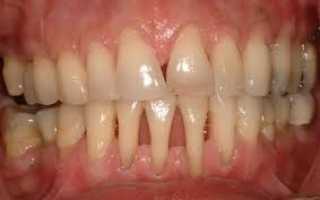

Крайне неприятным последствием пародонтоза является кровоточивость десен. Увеличение межзубных щелей и возникновение подвижности зубов. Оседание десен чревато оголением шеек и корней зубов и возникновению эффекта клиновидных зубов. Болезнь не только сопровождается болезненными ощущениями зубной эмали на термические и химические раздражители, но и существенно снижает самооценку больного. Болевые ощущения мешают полноценному питанию и общению, по утрам усиливается неприятный запах из ротовой полости.